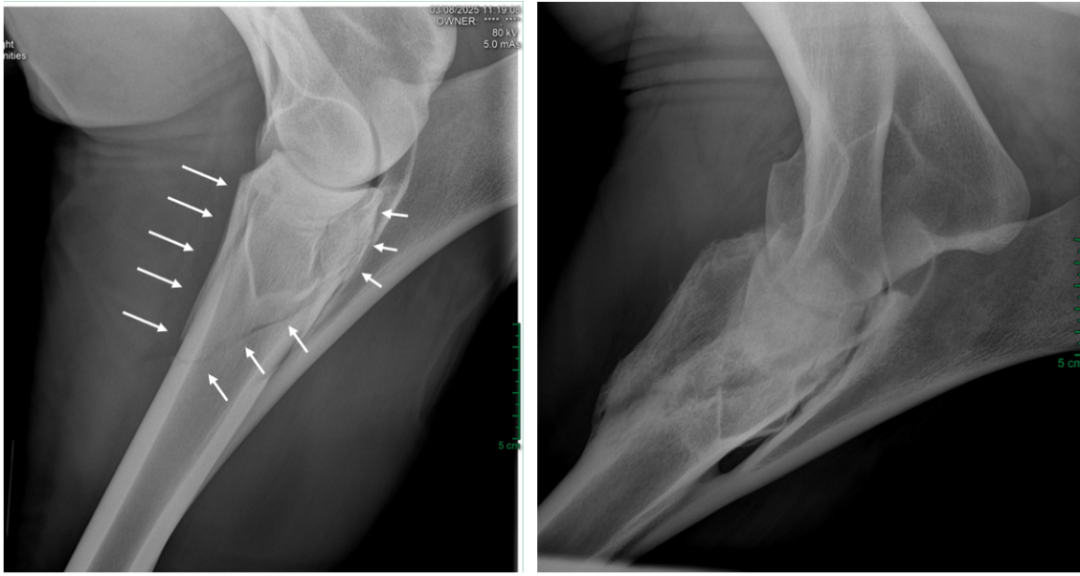

踢伤造成的成年马桡骨骨折,外固定保守治疗,6个月后复查长出骨痂。图源:王炜晗

一匹马在麻醉苏醒过程中发生肱骨粉碎性骨折